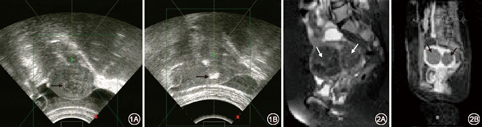

(1)仪器:采用重庆海扶(HIFU)技术有限公司研制的JC–200型聚焦超声肿瘤治疗系统。(2)方法:①术前检查及术前准备:术前行血、尿、便、肝肾功能、心电图常规检查,常规超声检查子宫的位置、形态、大小,子宫病变大小及其内部和周边血流信号。MRI磁场强度为0.35T,对盆腔行T1WI、T2WI扫描,显示子宫占位病变,病变血流情况以及子宫与周围组织脏器的关系。术前准备主要包括常规的皮肤准备及肠道准备,皮肤准备主要是备皮及预计治疗声通道区域皮肤的脱脂、脱气等;肠道准备主要是治疗前的导泻及清洁肠道,以避免气体对超声图像的干扰及减低肠道损伤的风险。②HIFU治疗:治疗时留置导尿、适当充盈膀胱(200~300 ml),具体充盈量根据术中情况来定,取俯卧位。治疗全过程对患者实施适当的镇静镇痛(芬太尼、咪达唑仑及吗啡)。患者下腹部浸入脱气水中,机载超声定位选择治疗区,声通道避开肠道和耻骨联合等。当病灶充分暴露,确定肌瘤范围后,拟定治疗范围,将每个肌瘤瘤体分为若干层面,按照由点到线,由线到面,由面到体的方式由深至浅逐层进行治疗,完成治疗计划。治疗参数:发射频率0.8 MHz,功率50~400 W,采用点扫描,每次点照射1~2 s,间隔1~3 s,重复6~12次,层厚5 mm。手术中根据患者手术中是否有不适反应适当调整治疗功率、位置及治疗时间,治疗总时间根据肌瘤大小1~4 h。③治疗中超声实时监控:治疗中机载超声可以实时观察肌瘤变化以及周围正常组织的情况,使能量聚焦在病灶区域而避免周围组织的损伤,当靶区出现明显灰度增加或团块状灰度,可明确该治疗区出现凝固性坏死,然后治疗下一个点,直到将整个计划治疗区完全覆盖。治疗时若患者出现腹部皮肤烧灼痛或腰骶部、臀部、下肢疼痛即停止辐照。治疗前后B超显示灰度即刻变化如图1。④随访:HIFU治疗后1、3和6个月对患者进行随访,包括血常规、超声或MRI,观察患者肌瘤大小、血供变化情况;详细了解并记录患者治疗后月经量有无减少、周期有无变化、有无贫血、痛经及不良反应发生等临床症状改善情况;经阴道超声及MRI评估HIFU治疗后消融灶体积、内部血流回声及图像改变情况,并与治疗前子宫瘤灶大小、体积及声像图表现进行比较,评价治疗效果,统计治疗显效、有效及无效率。治疗前后MRI对比变化见图2。